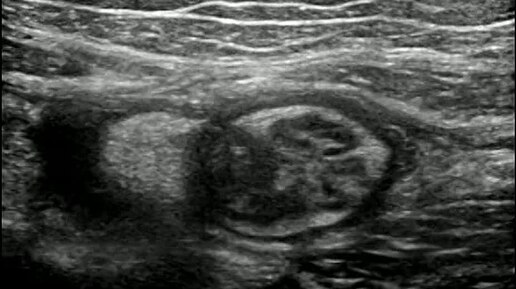

Видео к статье: "Свободная жидкость в брюшной полости"https://dzen.ru/a/Z-1KdOK-KyrjRiGF

Ультразвуковые находки от врача УЗД Зорина Я.П.